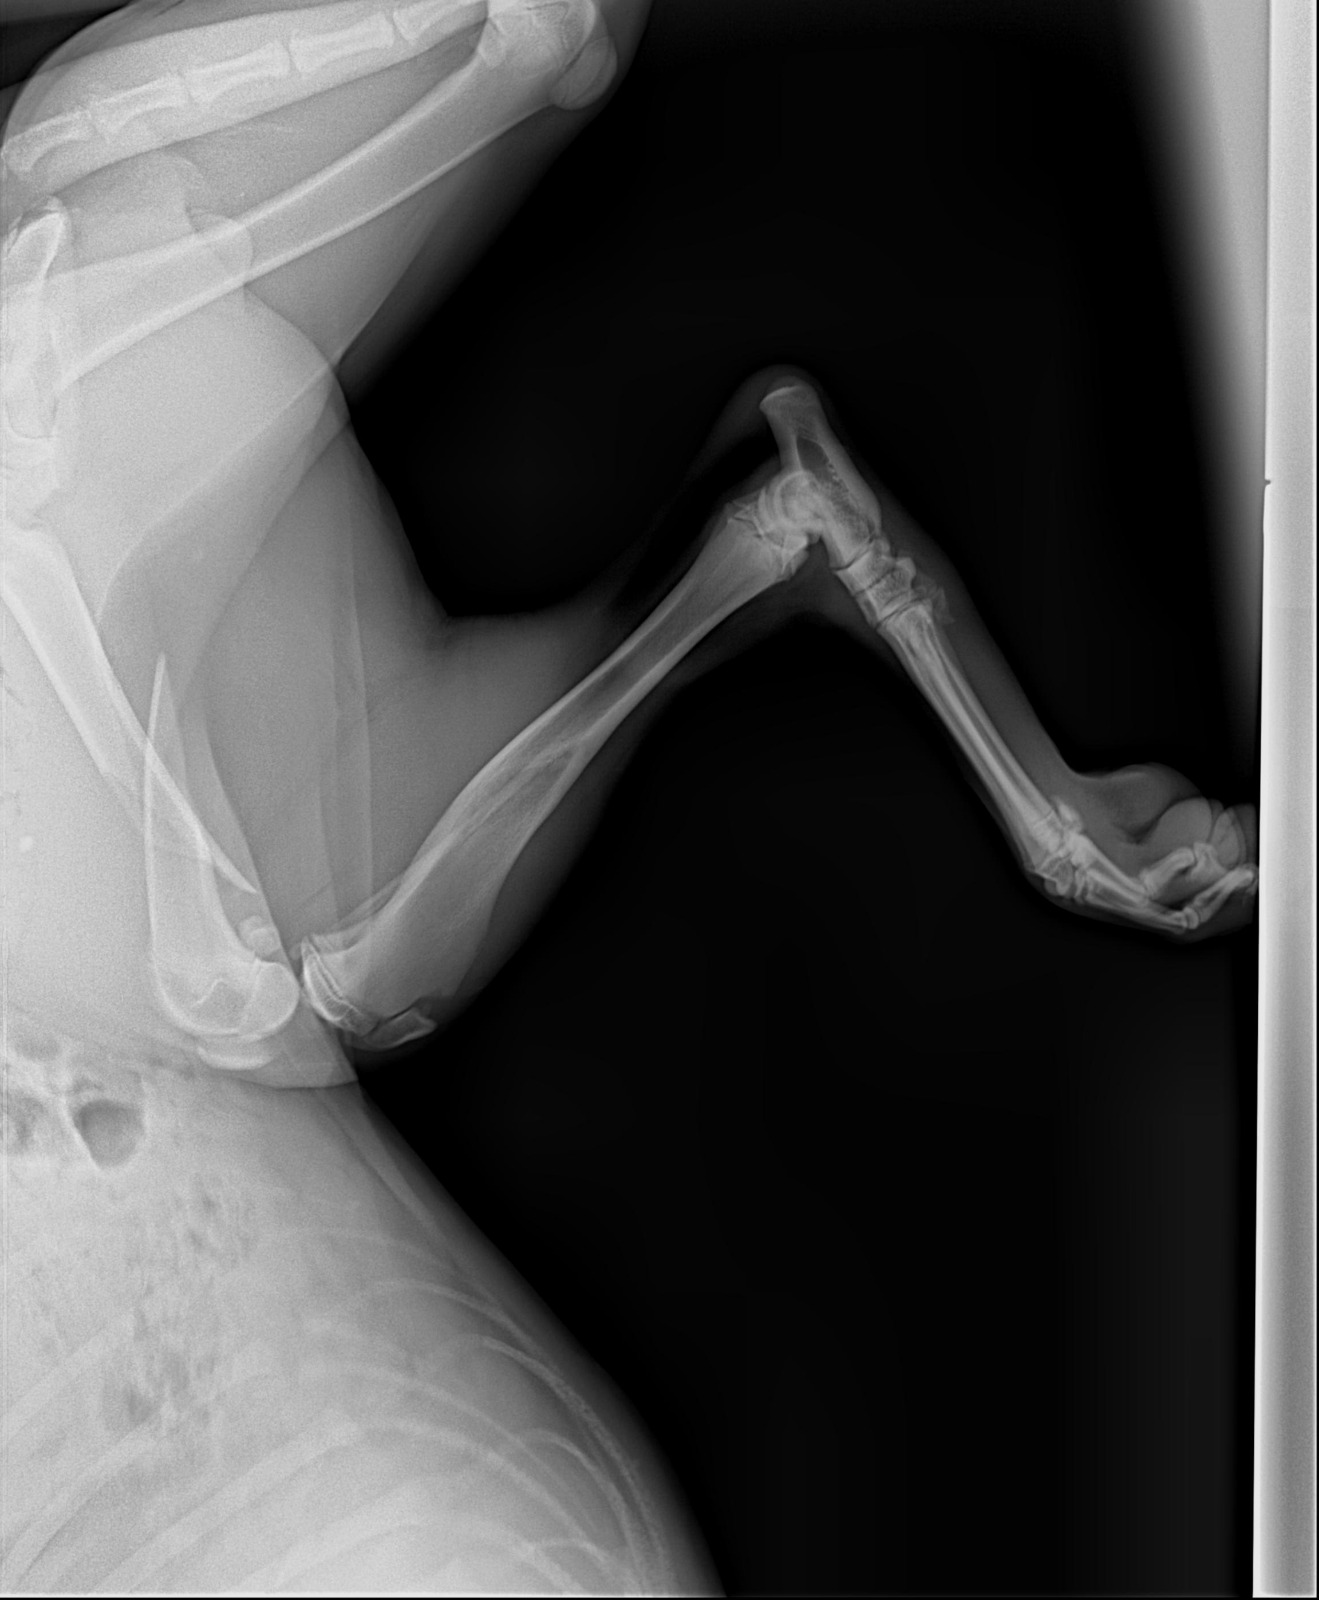

These dogs are in south lebanon rescued from war zone after being left behind. The one to the left was hit by a car and have a broken hip as shows frkm x rays and needs an urgent operation. It costs 650 usd as per the screenshot of chat with the vet. Please your help us needed. We can not afford as we are not working currently.